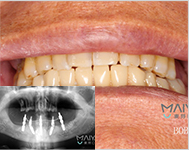

种植牙

技术优势:快速无痛、终身使用、舒适度高、类似真牙

种植方式:即刻用种植、前牙美学种植、ALL-ON-4即刻种植

适应症状:单颗牙缺失、多颗牙缺失、半口、全口无牙颌种植

麦芽全数字化精确种牙案例